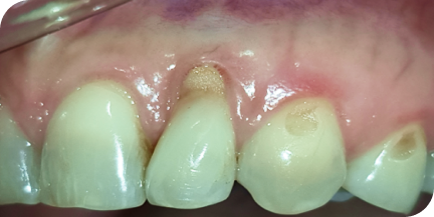

Пациент обратился с жалобами на оголенный корень зуба, повышенную чувствительность, на неэстетический вид зуба, так как зуб стал выглядеть длиннее, чем раньше.

После обследования поставили диагноз — рецессия десны.

Это патологическое состояние, при котором десна опускается вниз, корень зуба оголяется, появляется чувствительность зуба, эстетический дефект и возрастает риск развития другого патологического состояния — кариеса корня. В свою очередь, кариес корня — это показание к удалению зуба.

В данном клиническом случае провели микрохирургическую операцию по наращиванию десны с применением специального микроскопа. Это дало хороший, долгосрочный прогнозируемый результат.

ВАЖНО! Нужно понимать, что не у каждого оголенного корня можно нарастить десну. Ключевой фактор — стадия, на которой вы обратились. Есть стадии, на которых это невозможно, и единственным вариантом является УДАЛЕНИЕ ЗУБА!

Исходное состояние